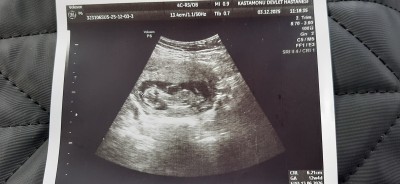

image

Bu da benim miniğim 12+5 oldum merakla bekliyoruz ☺ sağlıkla sağ salim kucağına alırsın inşallah canim 🥰

Kıza benziyor